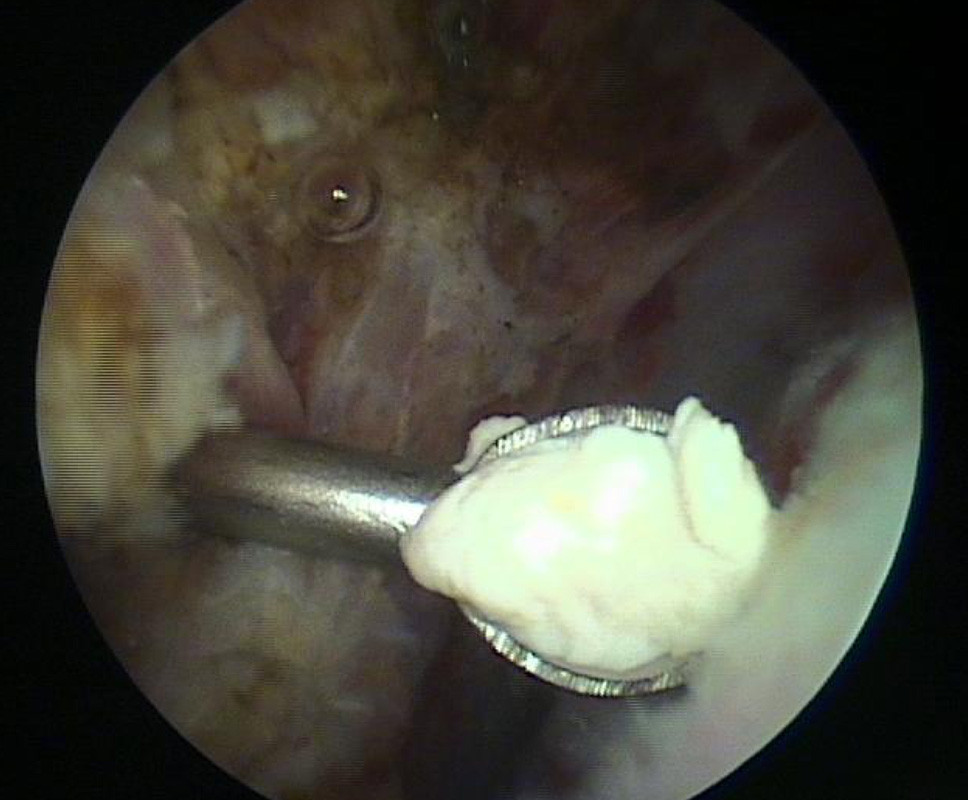

Manchmal liegt der Kalk auch auf der Sehne und führt zu einer starken Entzündung. (Bild 4)